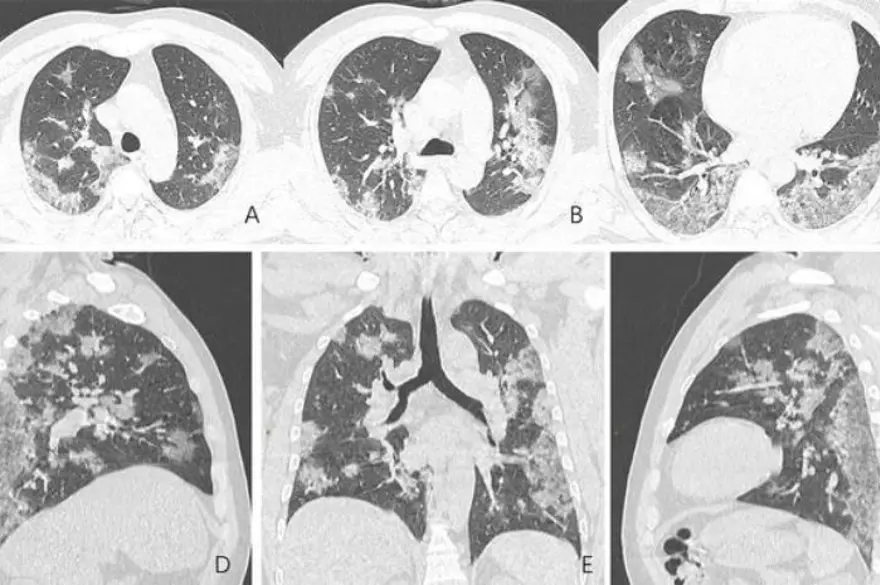

Diğer taraftan, A görüntüsüyle F görüntüsü karşılaştırıldığında, akciğer uzuvlarında bulunan sıvının, zaman içinde belirgin bir şekilde corona virüs nedeniyle arttığı görülebiliyor.

Solda yer alan fotoğrafta kırmızı olarak görülen alanlarda nodüller, sağ tarafta ise akciğer ve trakeanın üç boyutlu görüntüsü yer alıyor. Beyaz alanlarda corona virüsün tahribi görülüyor.

Japonya'dan döndükten sonra corona virüse yakalan Çin'in Sichuan eyaletinden 45 yaşındaki bir kadının taramalarında ise, corona virüsün akciğerinin sol üst lobunda ters hale edilmiş hale işareti oluşturdu.